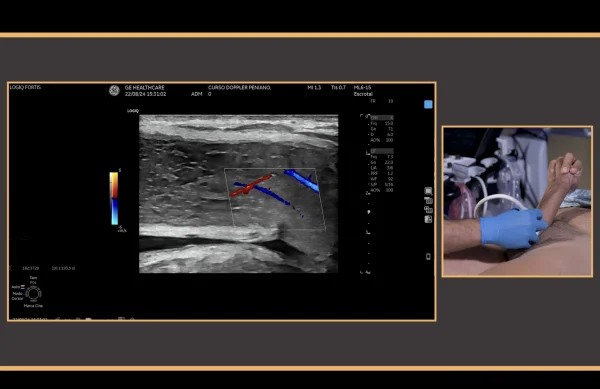

* PDU is the gold standard diagnostic modality in the vascular assessment of erectile function, and it is useful in the therapeutic decision-making process for patients with erectile dysfunction.

This video provides a step-by-step guidance in the conduction of hemodynamics studies using penile Doppler ultrasound (PDU). PDU is the gold standard diagnostic modality in the vascular assessment of erectile function, and it is useful in the therapeutic decision-making process for patients with erectile dysfunction. The video outlines the most important principles for an adequate exam conduction, which includes redosing of vasoactive agents for during erection induction, a rigidity-based assessment of hemodynamic parameters, and an effective detumescence protocol using reversal agents. The conduction of standard PDU examination of a 54 year-old man with erectile dysfunction is described.